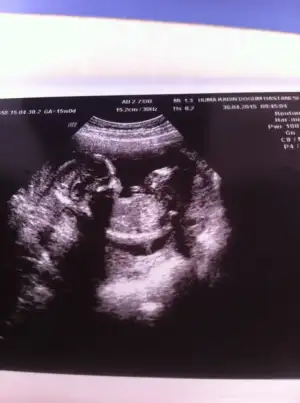

mrb arkadaşlar bugün 15 haftalık olduk kontrol vardı ve cinsiyetimize %51 den yüksek erkek dedi. resimler kalitesiz diyende var siz anlayabilirmisiniz merak beni öldürecek :)